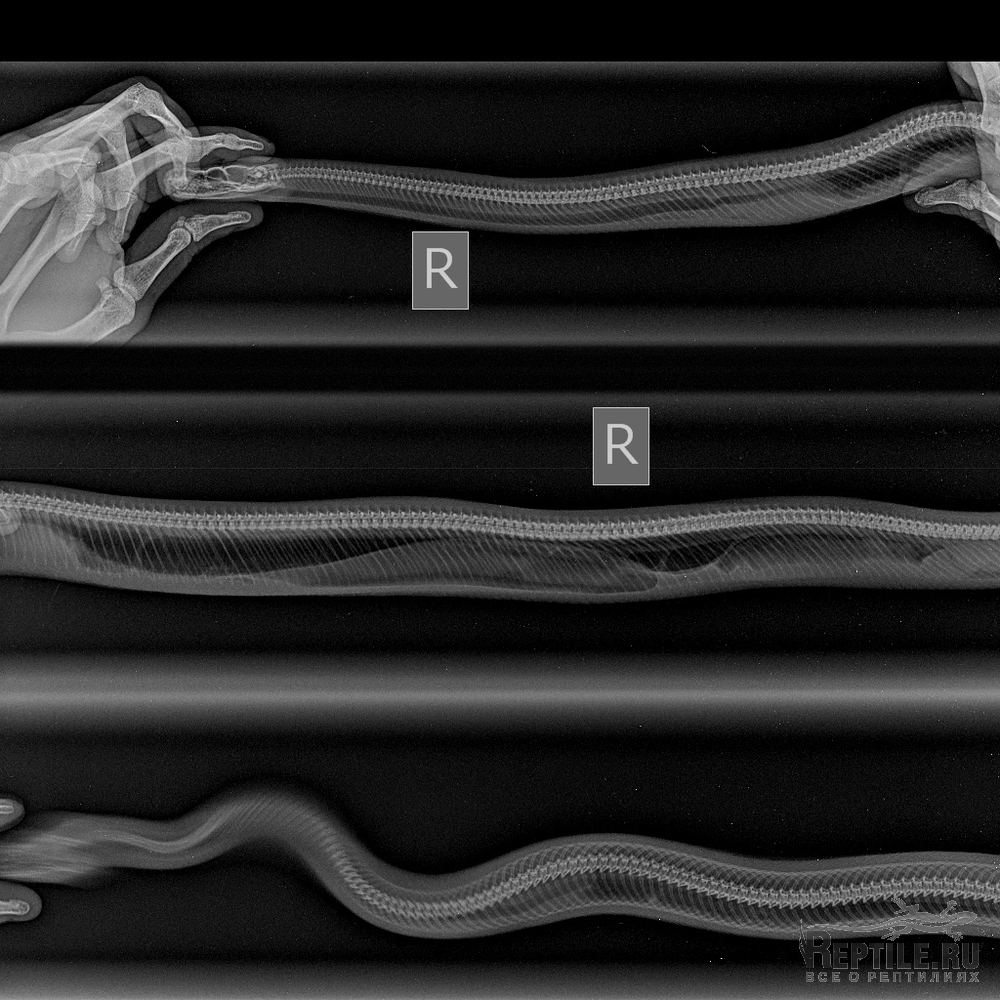

Поставили исходя из рентгенографии - травму трахеи.

Обратилась к герпетологу, сделали рентген, врач предположил травму от укуса КО. Или хроническое врожженное , на снимке видно уплотнение в трахеи, змее тяжело дышать. Все время лежит неподвижно. Колю по назначению Байтрил и Катозал.